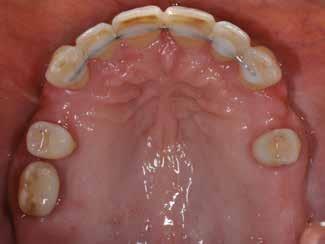

Den kliniske undersøgelse viser ingen symptomer fra muskler eller kæbeled. Ingen ledlyde ved åbne-/lukkebevægelse og ingen udsving ved åbne-/lukkebevægelse. Der er vertikalt overbid (VOB) 3-4 mm, horisontalt overbid (HOB) 1 mm, Angle kl. I med retroklination af såvel over- som underkæbeincisiver

(Fig. 6 A-D). Relativt flad Spee kurve. Ud fra TWES 2.0 graduering har pt. slid af 2. grad i over- og underkæbefront, dog har 1-1 slid af 3. grad. Incisiverne har skarpe incisalkanter med emaljefrakturer og emaljeinfraktioner (Fig. 6 C, D) samt udtalte dentinkonkaviteter incisalt (Fig. 6 E). Posteriort ses slid af 1.-2. grad, og der er mistanke om natlig bruksisme, selvom patienten ikke oplyser dette. Der er såvel attrition som erosion med cuppings på flere molarer samt hævede fyldninger med mindre frakturer (Fig. 6 F, G). Erosiv årsag kan ikke identificeres ud fra kostanamnese. Der ses tydelige slidfacetter i hele tandsættet generelt. Patienten har perfekt mundhygiejne, ingen caries, slimhindeforandringer eller patologiske pocher.